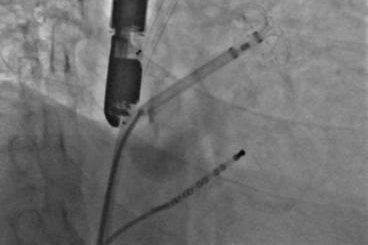

▲血栓位于心耳中段

▲半发展固定伞,推送至锚定位锁死血栓

开释后,DSA与TEE观察均无残存分流

实现后取出脑;ぷ爸,均未见血栓

其中首场公开演示的左心耳血栓封堵病例拥有极高难度,患者术前TEE显示左心耳血栓形成伴机化,血栓位于心耳中段,近中端絮状物显著 。封堵机遇只有一次,选型和操作稍有失误,城市增长手术风险 。因而手术采取全麻,并装置了抗栓塞脑动脉;ぷ爸,以削减术中风险 。通过TEE疏导下丈量左心耳大幼以及确认左心耳血栓地位,李岳春教授凭借自身丰硕经验最终决定使用LAmbre 2632型号,选取推送式植入法将左心耳血栓牢牢锁死于远端,并且封堵器一次成型,封堵成效极佳,实现后取出脑;ぷ爸,均未见血栓,顺利实现了此台高难度的手术,获得了学员们的一致认可 。